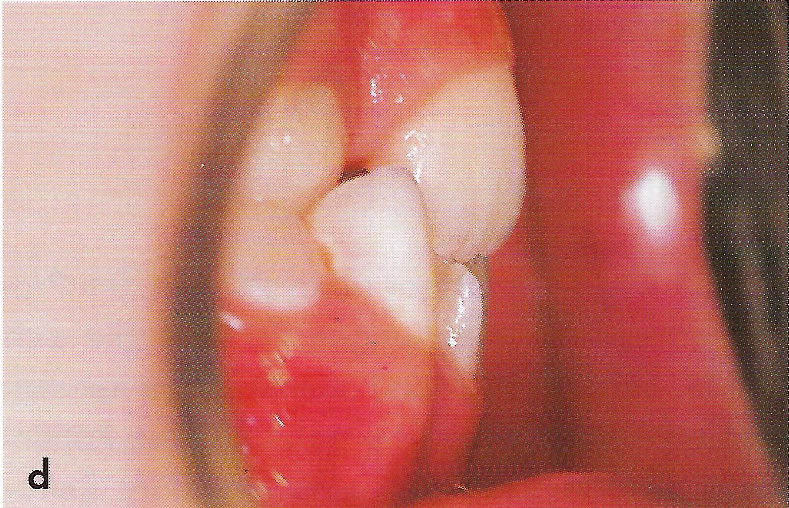

Abb. 1 a bis h Extra- und intraorale Ansicht der Patientin vor Behandlungsbeginn: Kopfbiß beziehungsweise umgekehrter Schneidezahnüberbiß und beidseitiger Kreuzbiß als Folge einer maxillären Hypoplasie sowie hälftenungleicher Mesialbiß infolge mandibulärer Verschiebung nach rechts.

• Ankylose Abb.1d

Diese Patientin war zu Behandlungsbeginn 7 Jahre alt. Sie hatte einen hälftenungleichen Mesialbiß infolge mandibulärer Verschiebung mit Kopfbiß beziehungsweise umgekehrter inzisaler Stufe, rechtsseitigem vollem Kreuzbiß und linksseitigem doppeltem Höckerbiß, maxillärer Kompression sowie Platzmangel in beiden Kiefern (Abb. 1 a bis h). Die kephalometrische Analyse ergab eine progene Kieferlagebeziehung, bedingt durch eine unterentwickelte Maxilla bei vertikalem Gesichtsschädelaufbau.